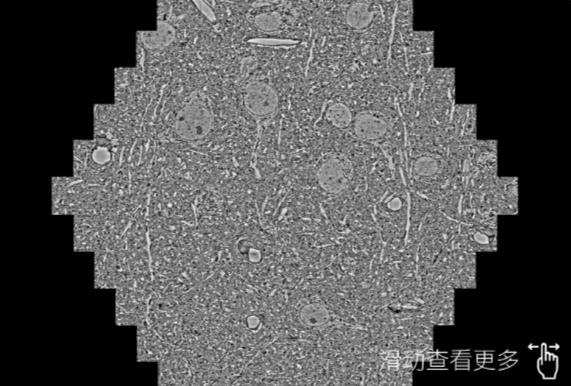

鼠脑切片。左图使用辽源蔡司辽源扫描电镜MultiSEM706对165μmx143pm面积区域成像,耗时仅需1.5秒。右图为鼠脑切片中30μm区域放大效果。样品由芝加哥大学B.Kasthuri提供。